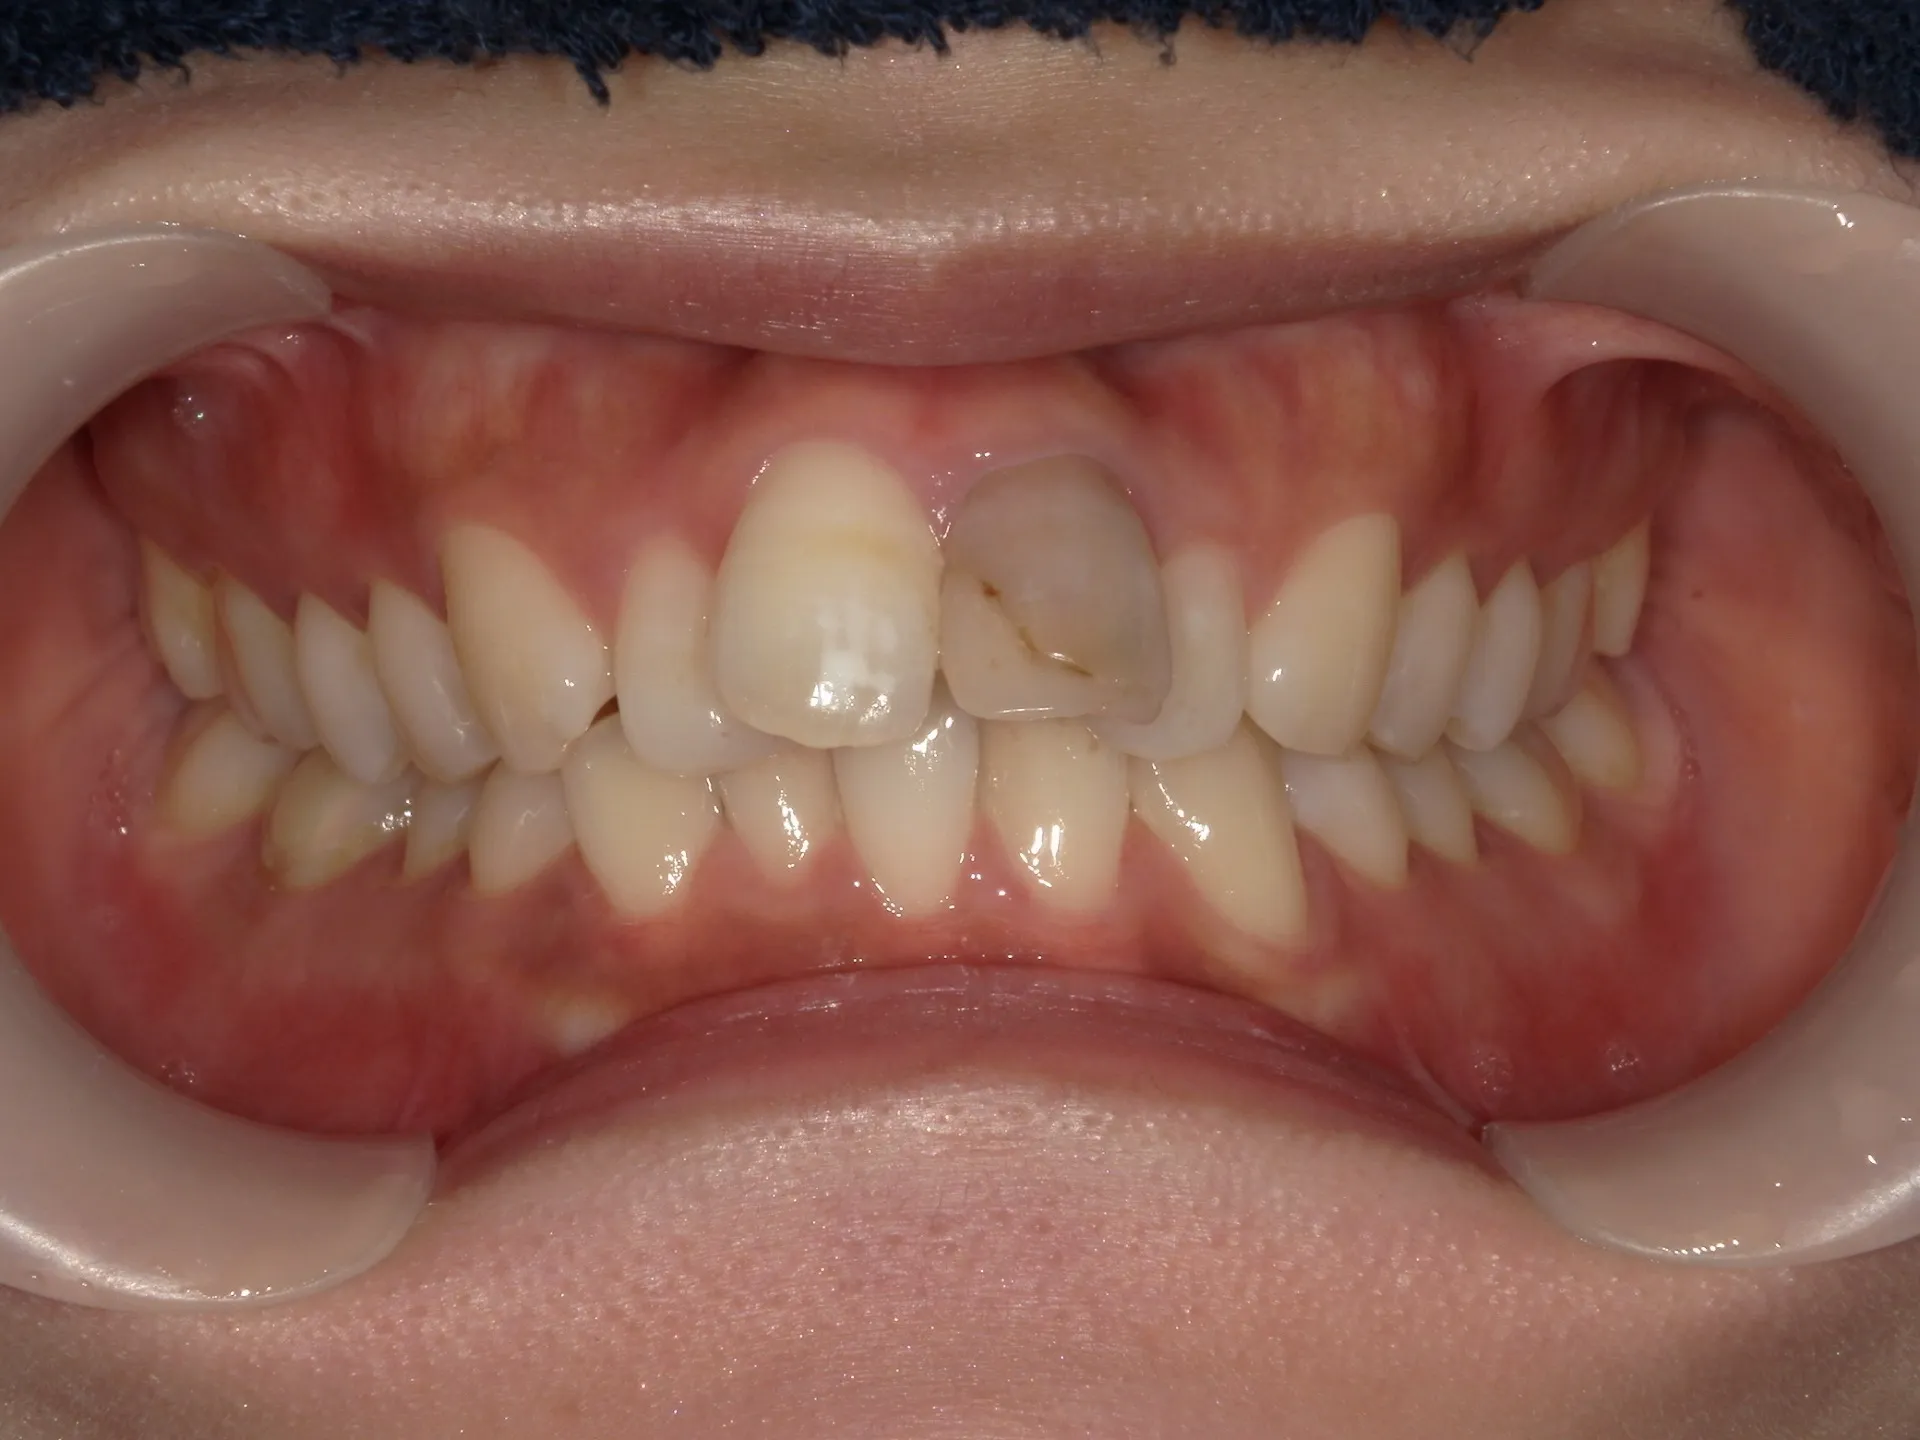

大きく変わる前歯の傾斜(歯並び)

大きく飛び出してしまった前歯の矯正と変色の治療を希望された症例をご紹介いたします。